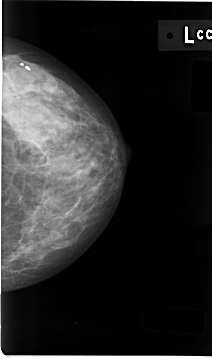

C_0008_1.LEFT_CC

LEFT_CC LINES 4664 PIXELS_PER_LINE 2744 BITS_PER_PIXEL 12 RESOLUTION 50 NON_OVERLAY